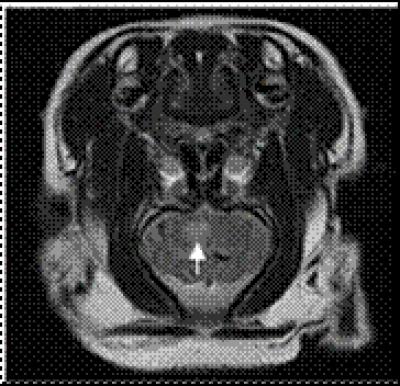

Rodents are frequently used as animal models for ischemic stroke studies induced by middle cerebral artery occlusion. However, their anatomic structure is significantly different from humans. Thus, recent studies have focused on developing stroke models in large animals with similar anatomic structure as the human brain. The swine have several properties resembling the human brain, including brain volume and weight, quantity of cortical gyri and the percentage of white matter to gray matter. These properties allow evaluation of conventional cerebral imaging techniques and simulation of some surgical approaches. Moreover, the swine is more cost-effective, easy to feed and obtain compared with non-human rodents, and are thus an ideal model. However, the abnormal capillary net at the branch of common carotid artery in swine makes it difficult to establish an ischemic stroke model by middle cerebral artery occlusion via the common carotid artery. According to a study in the Neural Regeneration Research (Vol. 8, No. 16, 2013), an ischemic stroke model was established successfully in the miniature pig by blocking the skull base retia with sodium alginate microspheres. These findings indicate that sodium alginate microspheres are a suitable embolic material for blocking the skull base retia in miniature pigs to establish an ischemic stroke models. This method challenges the concept that the swine cannot be used to establish models of ischemic cerebrovascular diseases, and provides a stable and reliable model for studying pathogenesis, pathophysiologic changes, molecular biologic changes and development of safe and effective drugs for cerebral infarction-induced brain ischemia.

Article: "Application of sodium alginate microspheres in ischemic stroke modeling in miniature pigs" by Yongchun Cui1, Yi Tian1, Yue Tang1, Liujun Jia1, Aili Wu1, Peng Peng1, Jianzhong Yang1, Hong Du1, Xiaojuan Wang2, Like Wu2 (1 State Key Laboratory of Cardiovascular Disease, Fuwai Hospital, National Center for Cardiovascular Diseases, Chinese Academy of Medical Sciences and Peking Union Medical College, Beijing 100037, China; 2 Wu Stem Cells Medical Center, Beijing Union Health Co., Ltd., Beijing 100070, China)

Cui YC, Tian Y, Tang Y, Jia LJ, Wu AL, Peng P, Yang JZ, Du H, Wang XJ, Wu LK. Application of sodium alginate microspheres in ischemic stroke modeling of miniature pigs. Neural Regen Res . 2013;8(16):1473-1480.